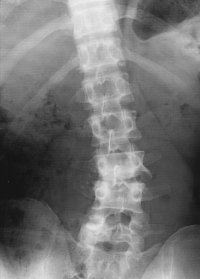

赤沈 45 mm/1 時間。血液所見:Hb 13.2 g/dL、白血球 9,000。CRP3.4 mg/dL。搬入時の腰椎エックス線写真と右半側臥位での腰椎造影 MRI及び入院3日目の仰臥位での腰椎 MRI の T2 強調像とを別に示す。